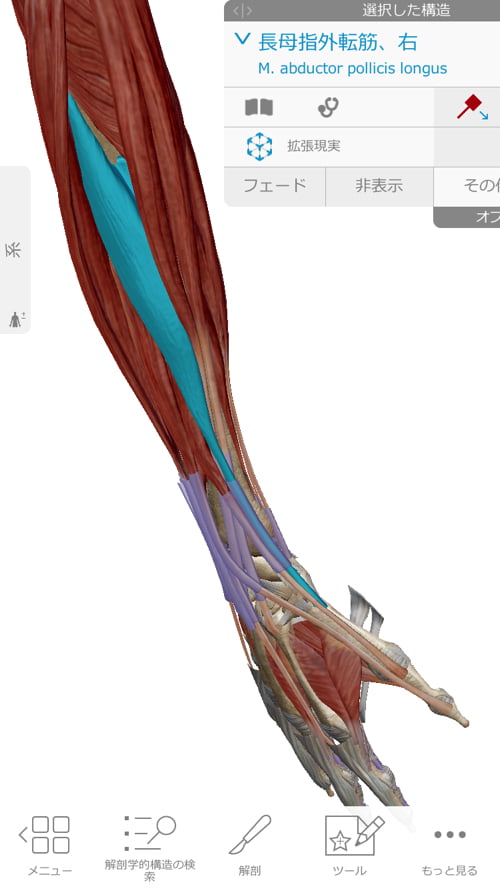

指からはこんな感じで肘まで繋がっている筋などが多数あります。

ここの部分の調整で「ばね指」の改善施術も一緒に行います。

それらが硬直や捩れを起こすと手首や肘もネジレてしまいます。